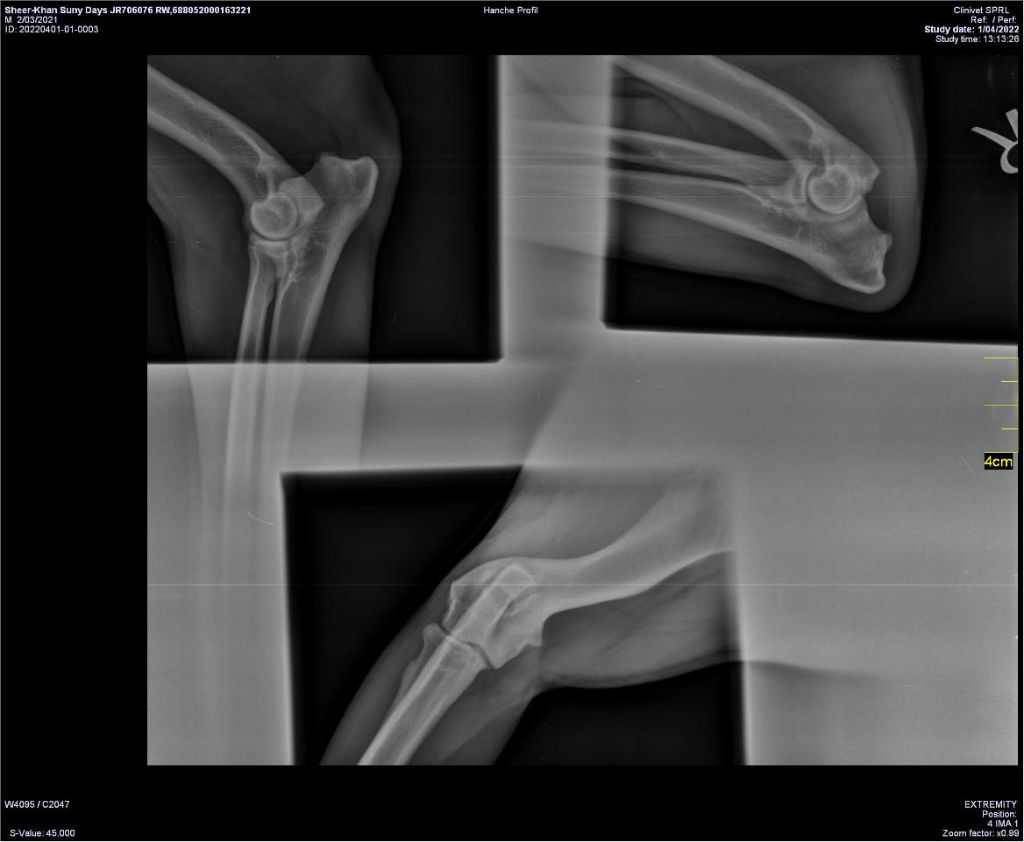

COUDES

Lecture officielle coudes